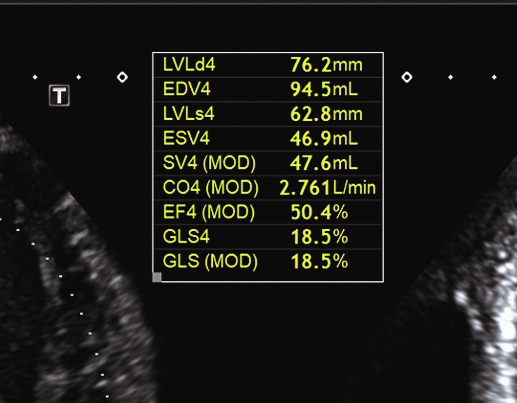

Глобальний поздовжний стрейн (GLS), включений в аналіз Авто ФВ в апікальному 4-камерному зрізі

Повністю автоматизоване вимірювання ФВ може бути виконано за лічені секунди, це технічно можливо та співставно з ручним трасуванням у 2D спекл-трекінгу4,5. Крім того, Авто ФВ є більш достовірною, ніж візуальна оцінка «на око», виконана навіть досвідченим фахівцем5. Такий автоматизований аналіз також надає інформацію (прорахування об’ємів ЛШ і ФВ, включно з глобальним поздовжним стрейном(GLS), яка, на відміну від традиційних методів оцінки ФВ і GLS, не має варіабельності4.

У пацієнтів з дисфункцією ЛШ, фракція викиду ЛШ і GLS мають лінійну залежність, фракції викиду ЛШ 35% відповідає значення GLS -11 або -127. Навпаки, фракція викиду ЛШ і GLS мають криволінійний зв’язок у пацієнтів із нормальною фракцією викиду ЛШ7. Перевагою включення GLS на додаток до ФВ ЛШ є його можливість виявляти на ранніх етапах захворювання до того, як фракція викиду ЛШ знизиться8.